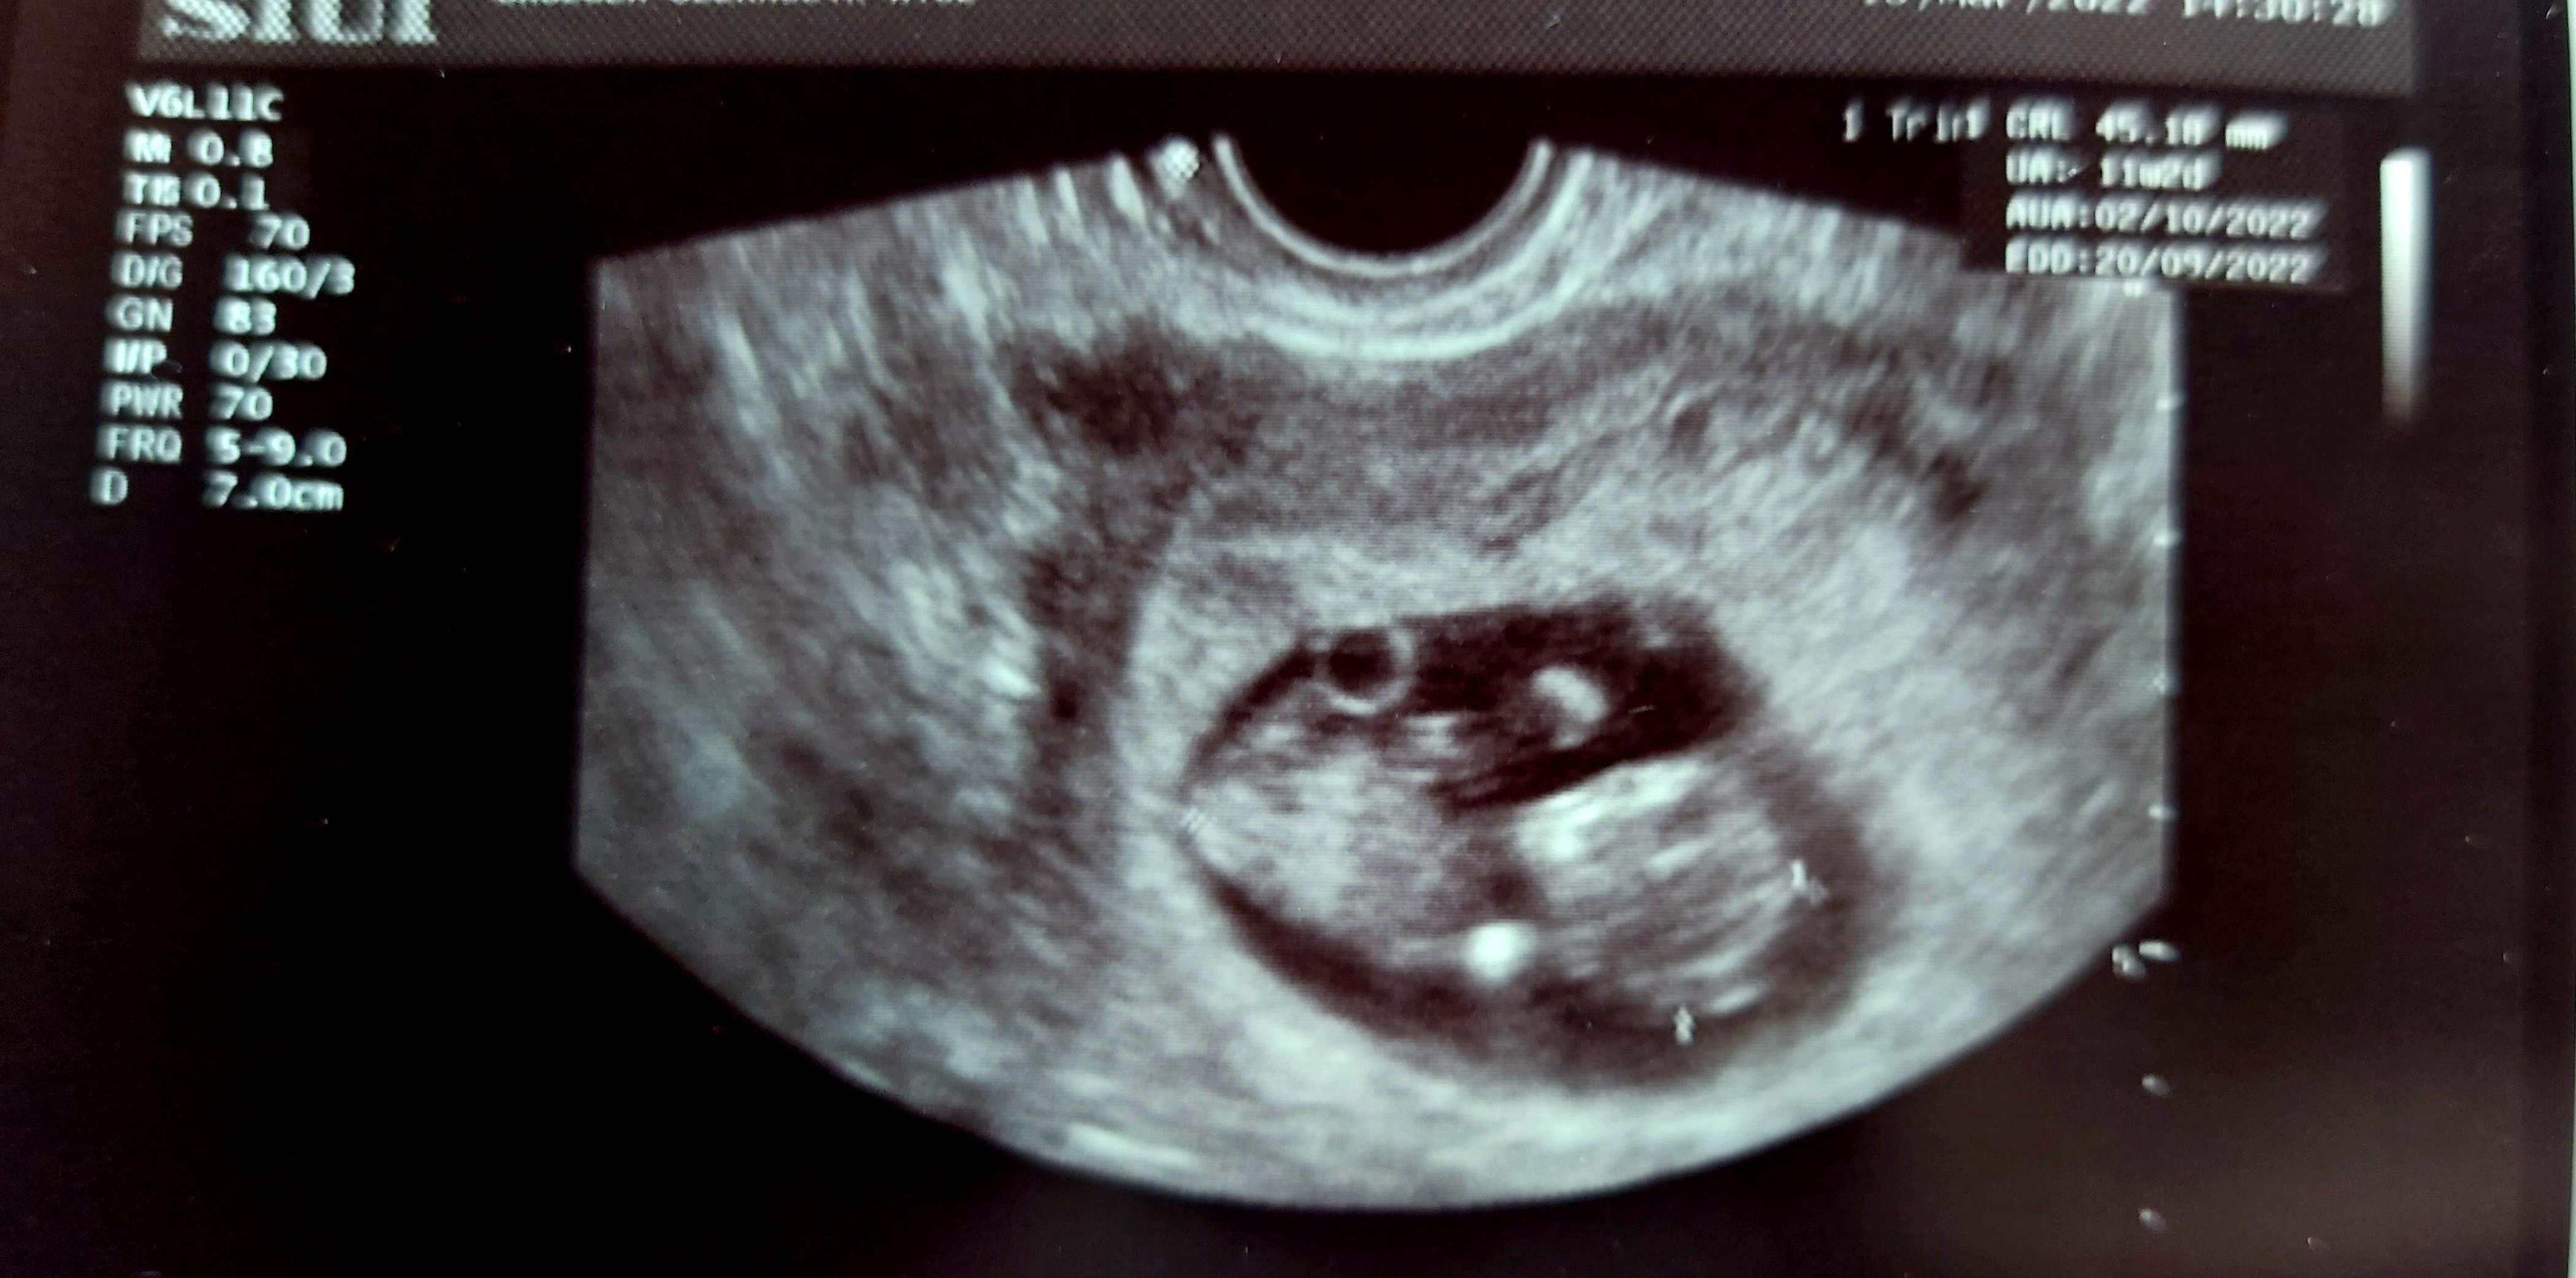

Super ze wszystko potwierdzone i serduszko bijeJa po wizycie

Ciąża potwiedzona, serduszko bijepoki co lekarz mówi ze ciaza młodsza z usg ok. 7tydz